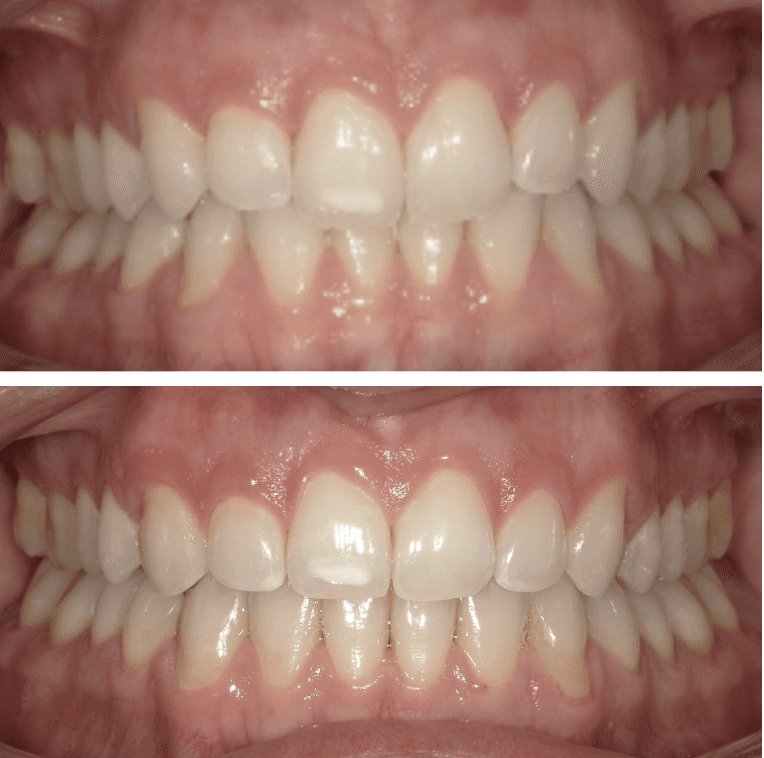

Mild Crowding

Female, 33 | Treatment time: 9 months

Diganosis: Moderate lower anterior crowding, square and narrow maxilla, rotated #19

Adjuncts: Attachments

Final results

INTRAORAL